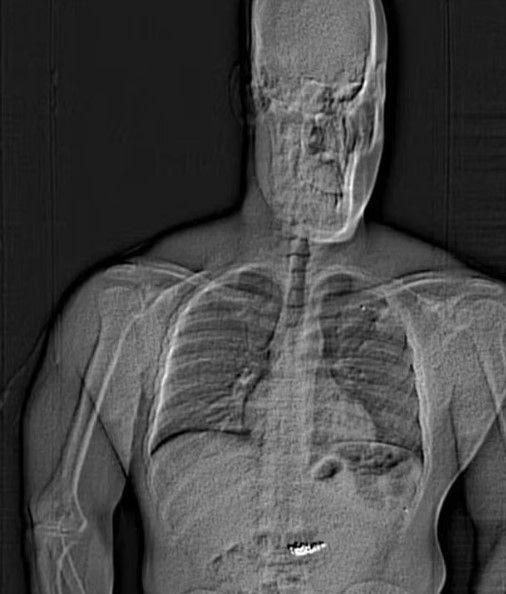

Λίγο αργότερα ένας αστυνομικός ακούγεται να λέει: «Κατάπιε κάτι». Ο 32χρονος ληστής συνελήφθη και μεταφέρθηκε στο νοσοκομείο, όπου αρνήθηκε να υποβληθεί την ακτινογραφία. Στη φυλακή υποχρεώθηκε να κάνει ακτινογραφία και τελικά εντοπίστηκαν ξένα αντικείμενα στο στομάχι του.

«Θα κατηγορηθώ για αυτό που βρίσκεται στο στομάχι μου;», φέρεται να ρώτησε ο ληστής. Αμέσως μετά επέστρεψε στο νοσοκομείο αλλά αρνήθηκε να πάρει καθαρκτικό με την αιτιολογία ότι είναι μουσουλμάνος και έτρωγε μόνο μετά τη δύση του ηλίου και πριν την ανατολή λόγω του Ραμαζανιού.

Τελικά μετά από εβδομάδες οι αρχές παρακολουθούσαν τις κενώσεις του εντέρου του ληστή και κατάφεραν να πάρουν τα διαμάντια.